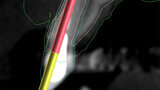

Fig. 3a: Planning the initial drill path using a custom implant design (red) to match the

diameter of the initial drill to reach the tooth apex. The abutment projection is shown in yellow.

3b: The simulated implant within the Triangle of Bone (red), placed to avoid the root fragment seen in yellow (white arrows).